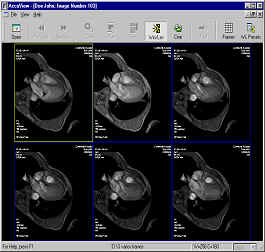

Pantalla de trabajo. Estudio DICOM abierto.

En la parte superior se muestran los datos del paciente, el clínico, fecha del estudio e institución donde se realizó dicho estudio.

En la parte central vemos la primera imagen que compone el estudio y, a la derecha, tres imágenes que se corresponden con los cortes axial, sagital y coronal, estos dos últimos reconstruidos a partir de las imágenes leídas, generalmente axiales. También se presenta cierta información técnica relativa a las imágenes, además de los valores de brillo y contraste y el porcentaje de zoom.

En la parte inferior se sitúan los controles y herramientas para manejar el estudio: botones de navegación por las imágenes, botón de animación (función "cine"), barras de control de los niveles de colores, un botón para cargar una paleta de color o un protocolo, controles de brillo y contraste, botones de zoom, un botón de inversión de la paleta, dos botones para aplicar filtros, un botón que permite restaurar los valores iniciales y un cuadro combinado en el que se pueden seleccionar las paletas o protocolos almacenados.